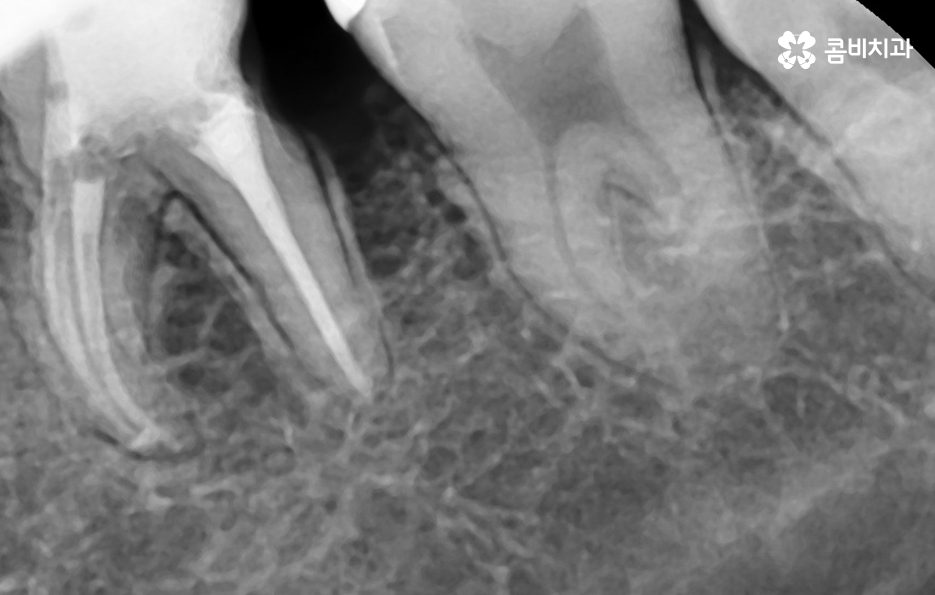

치아와 치아 사이가 맞닿는 부분은 평소 치실이나 치간칫솔을 사용하지 않는다면 칫솔질 만으로는 잘 닦이기 않기 때문에 충치가 자주 발생되는 부위는 아니지만 한번 발생되면 치아 양쪽으로 발생하기도 쉽고 치아 뿌리 쪽이나 신경 쪽에 가깝게 발생되는 경우도 많아서 간단히 레진으로 치료가 어려운 경우가 많고 보통 인레이나 크라운 치료로 이어지는 경우가 많이 있어요

치아 사이에 발생된 충치는 치아의 하단부에 발생되는 경우가 많기 때문에 신경이나 치아 뿌리 쪽에 가깝게 진행되는 경우가 많고 특히 어금니 처럼 저작력에 힘을 많이 받는 부위에 발생된 충치는 충치로 인해 치아가 약해지면서 치아가 깨지면서 문제가 드러나는 경우도 있기 때문에 치아의 파절로 까지 이어지는 경우도 있으므로 늦지 않게 치료하시길 권하고 있어요

치아 인접면에 발생된 충치가 신경치료나 뿌리 손상으로 이어지지 않도록 미리 막는 것이 중요하며 충치 치료를 할 때 자연치아를 되도록 보존하는 치료를 하는 것도 하나의 방법이 될 수 있어요